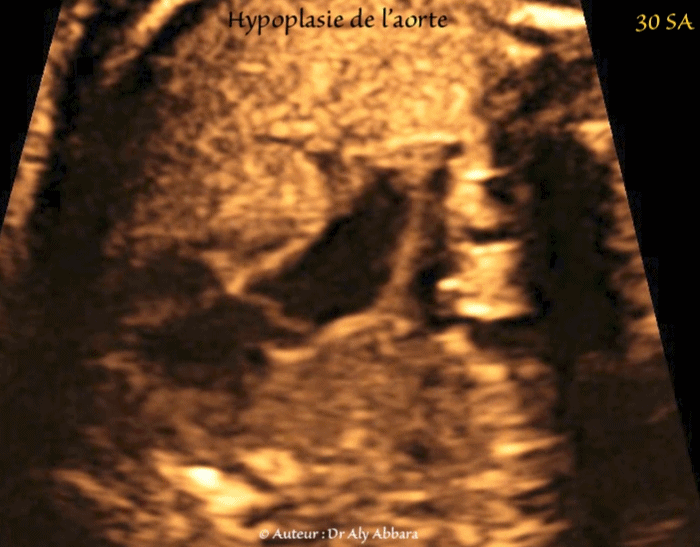

• Images échographiques montrant des multiples signes échographiques liés à la présence d'une hypoplasie de l'aorte dans sa portion ascendante et horizontale.

• Hypoplasie de l'aorte ascendante et de crosse de l'aorte : elle est visible sur la coupe des trois vaisseaux et de la trachée :

• le diamètre de l'aorte ascendant = 3,4 mm ;

• le diamètre de l'aorte horizontale = 2,5 mm ;

• à titre de comparaison, le diamètre du tronc pulmonaire = 8,5 mm.